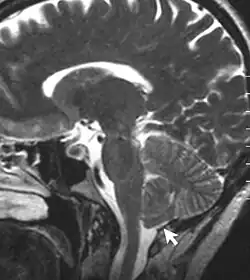

Zespół Arnolda-Chiariego (malformacja Arnolda-Chiariego, aktualna nazwa: malformacje Chiariego ang. Arnold-Chiari malformation, Chiari malformations, ACM, CM) – malformacja mózgowia polegająca na przemieszczeniu struktur tyłomózgowia do kanału kręgowego. Może współistnieć z przepukliną oponowo-rdzeniową[2]. Według najnowszej nomenklatury termin ,,malformacja Arnolda-Chiariego" zarezerwowany jest dla malformacji Chiari typu 2 (dziecięcy), a termin ,,malformacja Chiari" typowo odnosi się do malformacji Chiari typu 1 (dorosłych). Z uwagi na wprowadzone typy 1.5 i 0 używa się obecnie cyfr arabskich, zamiast rzymskich[3]

| 2 | Malformacja Arnolda-Chiariego. Typ dziecięcy. Przemieszczenie robaka móżdżku, opuszki i mostu łącznie z komorą IV. Zwykle związane z mielomeningocele (rozszczep kręgosłupa) i wodogłowiem. |